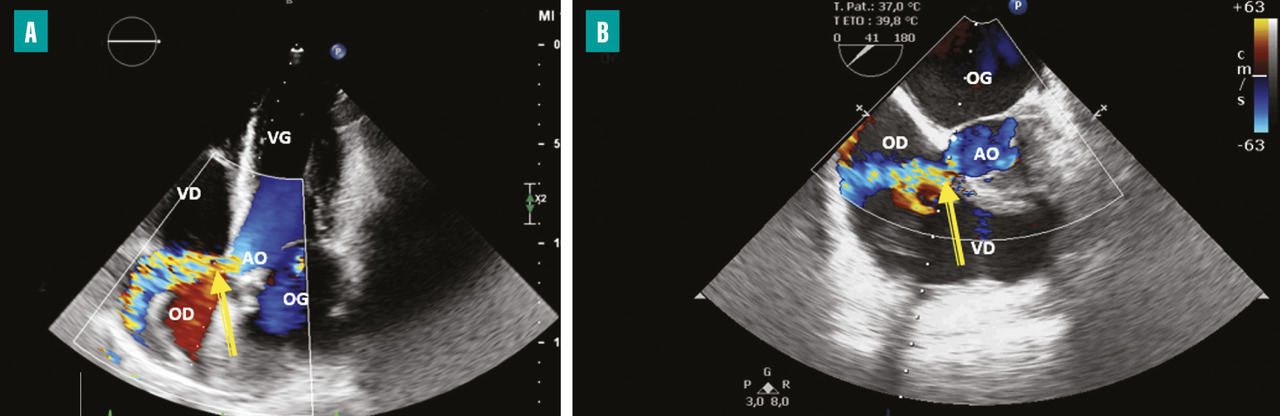

L’apparition à l’échographie cardiaque d’un abcès périvalvulaire ou périprothétique aortique (fig. 3 ) ou mitral est une complication grave de l’EI. L’abcès est plus fréquent dans les EI sur prothèses valvulaires (50 à 80 % contre 10 à 40 % sur valves natives). L’ETO est plus sensible que l’ETT pour ce diagnostic (notamment pour les localisations postérieures)2 et le scanner cardiaque est très performant pour la recherche d’abcès sur prothèse. La détersion de l’abcès peut être à l’origine de fistules entre les différentes cavités cardiaques (fig. 4 ). La fistulisation se fait le plus souvent dans la chambre de chasse du ventricule gauche. Les fistules intracardiaques dans l’oreillette gauche ou droite peuvent être à l’origine d’un tableau d’insuffisance cardiaque et compliquent le geste chirurgical.

– à l’évolution locale de l’infection par une extension périvalvulaire ou périprothétique des lésions et la formation d’un abcès (fig. 3 ) ou d’une fistule intracardiaque (fig. 4 ).

En cas de sepsis non contrôlé, il est impératif de refaire des hémocultures, de réaliser une surveillance rapprochée en ETT et en ETO, à la recherche d’un abcès périvalvulaire ou périprothétique. Un scanner thoraco-abdomino-pelvien et cérébral ou un TEP-scan est demandé, à la recherche d’un foyer infectieux embolique.